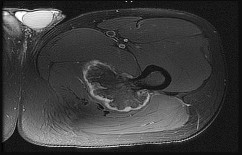

Question 25

A 48-year-old female presents with chronic, dull pain in her right proximal humerus that is worse at night. Radiographs demonstrate a well-circumscribed, lytic lesion with central 'popcorn' calcifications. MRI confirms a cartilaginous matrix, and cortical endosteal scalloping is present measuring 80% of the cortical thickness.

What is the most appropriate definitive management?

Explanation

The clinical presentation (pain at night) and radiographic findings (endosteal scalloping >2/3 of the cortical thickness, popcorn calcifications) are highly suspicious for a chondrosarcoma rather than a benign enchondroma. Low to intermediate-grade chondrosarcomas are managed with wide surgical resection, as they do not respond well to chemotherapy or radiation therapy.